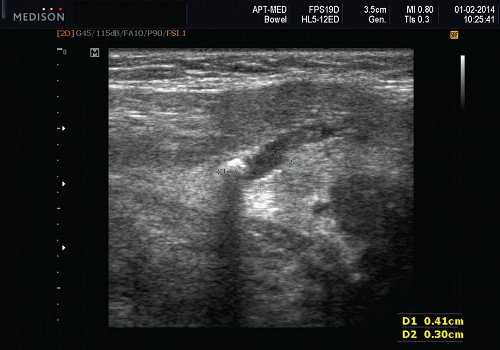

Рис. 5. Камень протока поднижнечелюстной слюнной железы.

Рис. 7. Камень в протоке поднижнечелюстной слюнной железы.